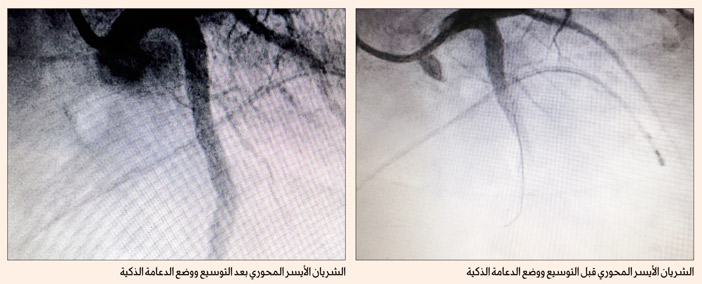

وأظهرت القسطرة التشخيصية بالقلب وجود انسداد كامل بالشريان الأيسر النازل، مع وجود جلطة كبيرة في دعامة سابقة، تم وضعها للمريض من قبل؛ الأمر الذي قرر معه الفريق الطبي القيام بإجراء قسطرة علاجية بالقلب لفتح وتوسيع الشريان والدعامة القديمة، ومن ثم نُقل المريض لقسم رعاية القلب لاستكمال العلاج الدوائي، ومتابعة حالته. وبفضل من الله، ثم يقظة الفريق الطبي لقسم القلب، تم إنقاذ حياة المريض، واستقرار حالته.